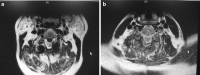

Methods: A 49-year-old Chinese male presented with a progressive cervical myelopathy (C-JOA score 11 immediately pre-op). Segmental OPLL at the C2-3 disk space was visible, together with invagination of the bilaterally hypoplastic C2 lamina into the spinal canal. Signal abnormalities of the spinal cord were evident on both T1 and T2 sequences.